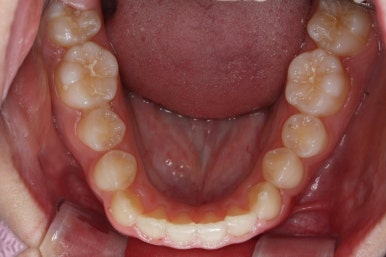

치료 종료 시점에는 위아래 앞니 모두 안쪽에 유지장치를 붙이고 있는 것을 볼 수 있습니다.

교정 중에 양치가 잘 되지 않아 치료 후 모습에서 잇몸이 부어있는 모습도 보이는데 양치질을 잘 해주면 금방 좋아질 수 있습니다.

앞니가 매우 가지런해졌고 예뻐졌네요.